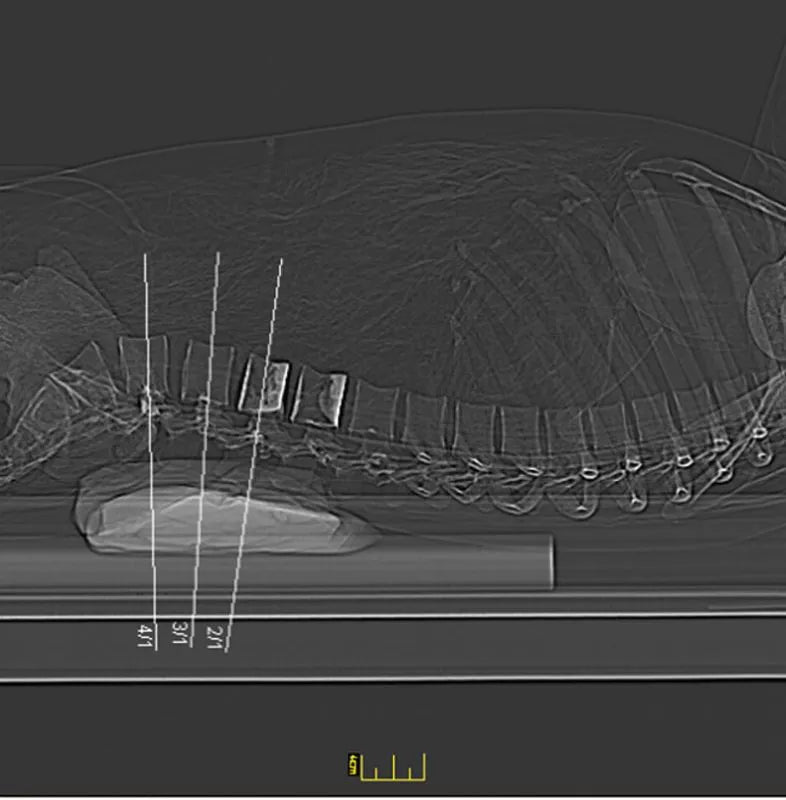

The whole-body X-ray phantom serves for practical training in projection radiography as well as in positioning and positioning techniques. It enables the production of realistic X-ray images under training conditions and depicts anatomical structures in their natural size.

The phantom contains a natural human skeleton. Additionally, the outlines of the larynx, lungs, heart, and kidneys are integrated, appearing as shadows on the X-ray images. This allows for the creation of images that accurately reflect the conditions found in patients. The use of a real skeleton enables the identification of bony landmarks that are not visible in plastic models.

The joints are mounted with full mobility, allowing positioning in common radiological standard positions, including special positions such as the frog position and pronation and supination of the forearm. The arms can be raised, so the phantom can also be used for bone examinations in CT scans. Particular attention was paid during assembly to the realistic representation of the joint spaces.